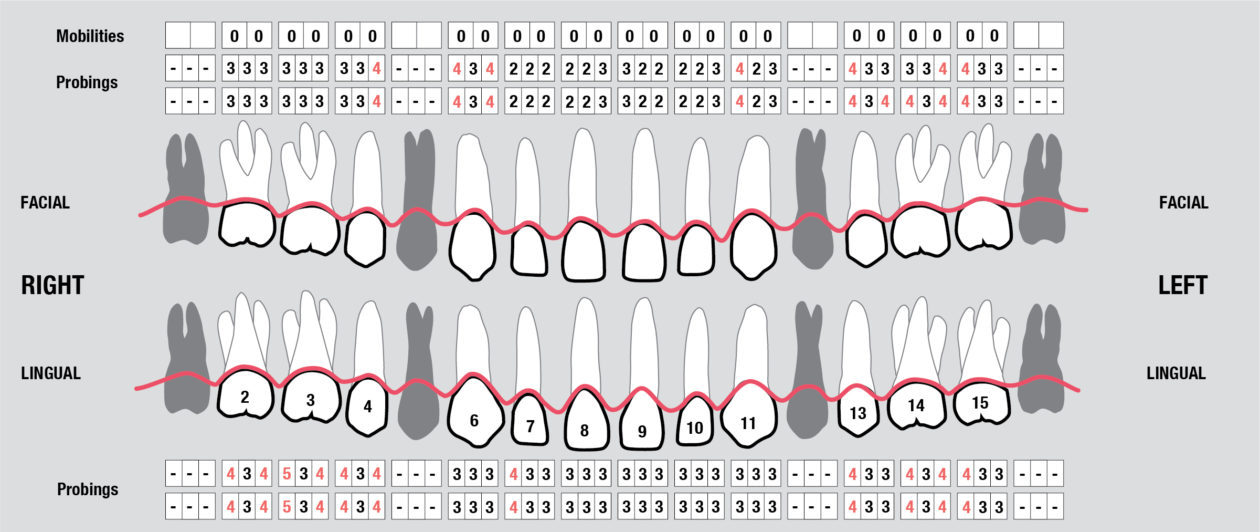

Full Mouth Radiographic Series, Maxillary and Mandibular Intraoral Scans, Digital Jaw Relation Recording with a Leaf Gauge, Complete Photographic Series, Periodontal Charting, Restorative Charting.